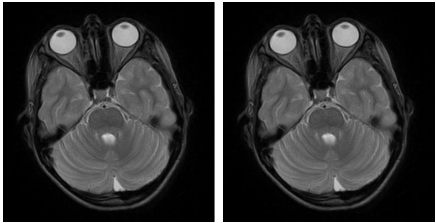

Unilateral Palsy of Palate which is acquired in nature is a rare entity, mostly affecting children. Patient usually presents with sudden onset of nasal regurgitation of fluids, rhinolalia and asymmetric movement of palate. The diagnosis is established only after exclusion of major causes such as infection, trauma, tumor, brain stem lesion etc. it is termed idiopathic when all potential causes are ruled out. The disease is usually self limiting and recovery is excellent. We report a case of twelve year old boy who presented in opd with complaints of regurgitation of fluids from unilateral nostril and nasal speech. Clinical examination was done followed by MRI brain which was unremarkable. Final diagnosis, unilateral isolated temporary idiopathic palsy of palate was established. Patient had complete recovery within ten days of tapering methyl prednisolone therapy with no residual paralysis on follow up.